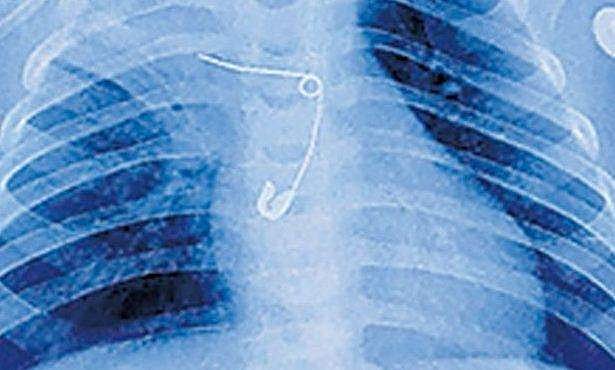

സുചി വിഴുങ്ങിയ കുഞ്ഞിന്റെ എക്‌സറേ ചിത്രം

അന്നനാളത്തില്‍ കുടുങ്ങി സേഫ്റ്റി പിന്‍, 8 മാസം പ്രായമുള്ള കുഞ്ഞിനെ രക്ഷിച്ചു

മുളങ്കുന്നത്തുകാവ്: സൂചി വിഴുങ്ങിയതിനെ തുടർന്ന് ആരോ​ഗ്യനില മോശമായ കുഞ്ഞ് ജീവിതത്തിലേക്ക്. സുചി വിഴുങ്ങിയതിനെ തുടർന്ന് എട്ട് മാസം പ്രായമായ കുഞ്ഞ് അന്നനാളം, ശ്വാസകോശം, തലച്ചോറ് എന്നിവയ്ക്ക് അസുഖം ബാധിച്ചാണ് മെഡിക്കൽ കോളജ് ആശുപത്രിയിൽ ചികിത്സ തേടിയത്.

സേഫ്റ്റി പിൻ പുറത്തെടുക്കാൻ ഡോക്ടർമാർക്കായി.  ജനുവരി 19നാണ് മണ്ണുത്തി വല്ലച്ചിറ വീട്ടിൽ വിനോദ് - ദീപ ദമ്പതികളുടെ മകനെ അബോധാവസ്ഥയിൽ മെഡിക്കൽ കോളജ് ആശുപത്രിയിൽ എത്തിച്ചത്. പ്രതിരോധ കുത്തിവയ്പിന് കൊണ്ടുപോയപ്പോൾ കുഞ്ഞ് രക്തം ഛർദ്ദി. ആശുപത്രിയിലേക്കുള്ള യാത്രയ്ക്കിടെ ഒരു വശം തളരുകയും അബോധാവസ്ഥയിലാവുകയും ചെയ്തു.

ഇതിന് ശേഷം നടത്തിയ പരിശോധനയിലാണ് അന്നനാളത്തിൽ സൂചി കണ്ടെത്തിയത്. മൂന്നാഴ്ചത്തെ പരിചരണത്തിനു ശേഷം ഇപ്പോൾ വെന്റിലേറ്ററിന്റെ സഹായമില്ലാതെ ശ്വസിക്കുന്നതിനും ഭക്ഷണം ഇറക്കുന്നതിനും കുഞ്ഞിന് കഴിയുന്നുണ്ട്.